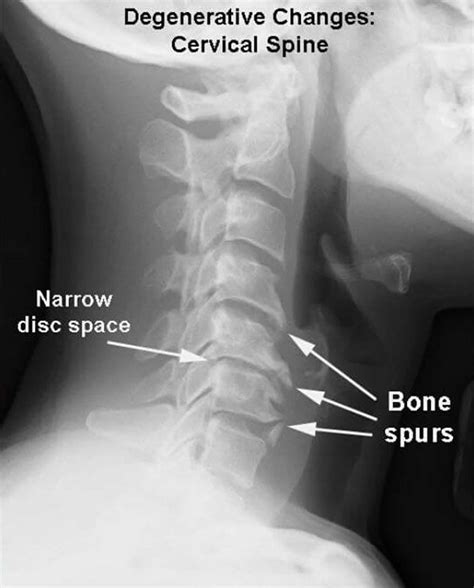

Arthritis in the neck occurs when the cartilage between the vertebrae in the cervical spine wears down, leading to inflammation and pain. This condition is often associated with aging but can also result from injuries, infections, or genetic factors. The most common types of arthritis affecting the neck are osteoarthritis and rheumatoid arthritis.

• Osteoarthritis: This is the most common type, caused by the wear and tear of the cartilage between the vertebrae.

• Imaging Tests: X-rays, MRI, or CT scans to visualize the bones and soft tissues in the neck.